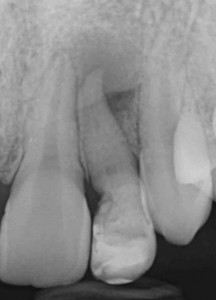

Con l’ausilio della Cone Beam sono riuscito a identificare che il dente aveva due canali e una radice molto palatoversa: per accedere a questi canali, separati tra loro dall’istmo di smalto invaginato, potevo fare una cavità perpendicolare al dente a livello vestibolare e una palatina.

Non ho smontato subito il composito perché mi serviva a riconoscere i reperi che mi ero cercato sulla tac.

La prima cavità, fuori dagli schemi, ho preferito farla senza diga per capire meglio l’inclinazione. Guarda che spettacolo la cavità di accesso!

Una volta trovato il canale con l’accesso più difficile e sapendo che un secondo canale decorreva parallelo a questo dal lato palatino il resto è stato relativamente semplice.

Ora Maddalena, così si chiama la ragazzina di questo dens in dente, con un piccolo allungamento di corona clinica seguito da limatura del margine incisale e una semplice otturazione di 12 e una corona in disilicato preparata su questo dens in dente, può tornare a sorridere. Ecco la foto e la rx a sei mesi dal caso finito. Tutto perfetto! Il 22 sta guarendo e le gengive e i denti stanno alla grande! Il brillantino invece ha perso il diamantino! ?